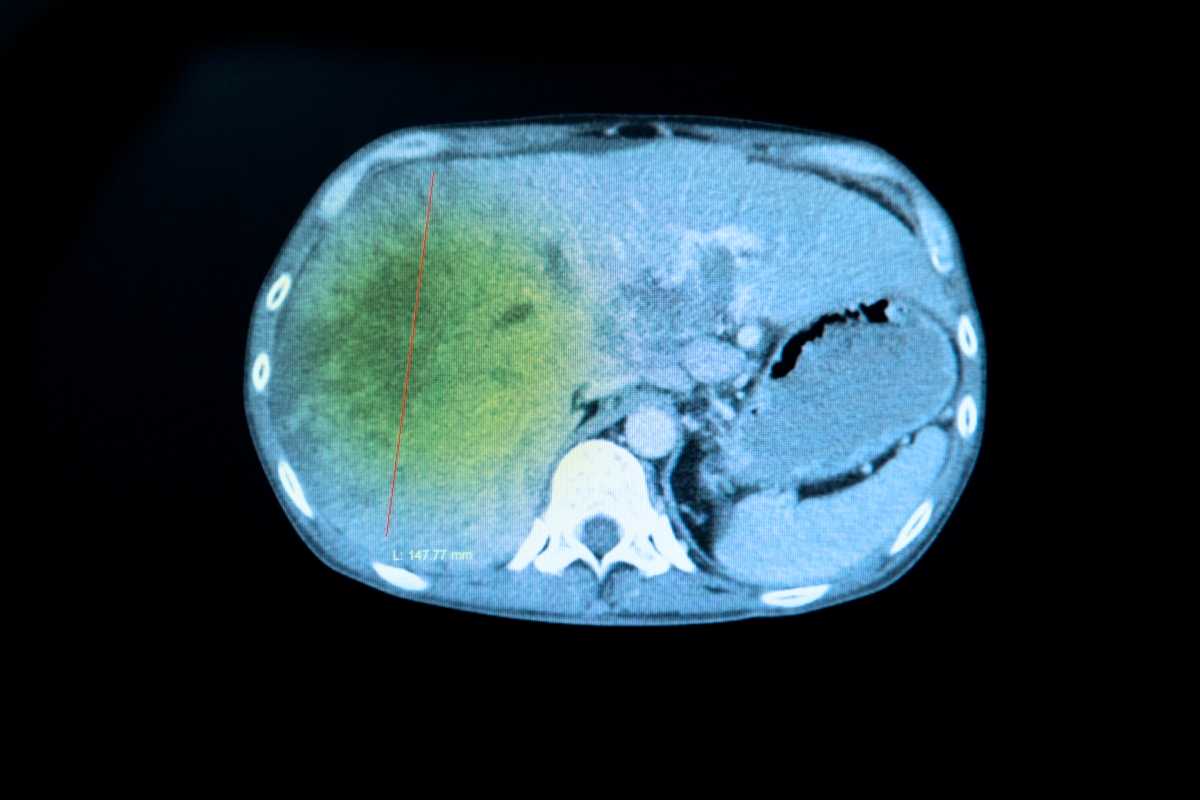

We prepare our residents for their careers as physicians with a training that emphasizes hands-on teaching and graded independence. Our Diagnostic Radiology Residents learn to dictate cases independently through apprentice-style teaching at the workstation and an extensive didactic teaching curriculum, while our Integrated Interventional Radiology Residents gain valuable clinical experience by practicing in multiple environments and managing patient care. Each resident sees a high volume of cases, including severe cases in our NCI Cancer Center and Liver Transplant Program. Specialty collaboration, direct feedback, collegiality and research opportunities allow every resident to maximize their potential.